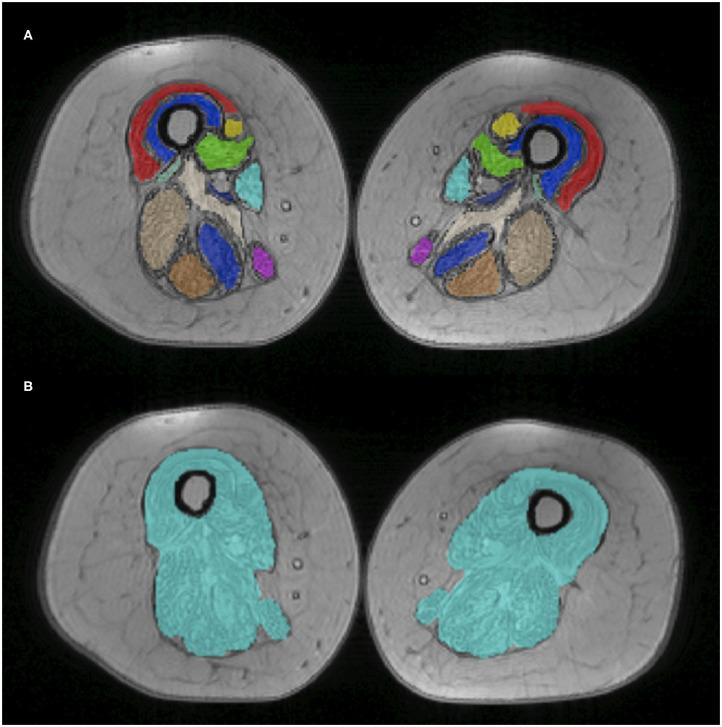

Nusinersen is a recent promising therapy approved for the treatment of spinal muscular atrophy (SMA), a rare disease characterized by the degeneration of alpha motor neurons (αMN) in the spinal cord (SC) leading to progressive muscle atrophy and dysfunction. Muscle and cervical SC quantitative magnetic resonance imaging (qMRI) has never been used to monitor drug treatment in SMA. The aim of this pilot study is to investigate whether qMRI can provide useful biomarkers for monitoring treatment efficacy in SMA. Three adult SMA 3a patients under treatment with nusinersen underwent longitudinal clinical and qMRI examinations every 4 months from baseline to 21-month follow-up. The qMRI protocol aimed to quantify thigh muscle fat fraction (FF) and water-T2 (w-T2) and to characterize SC volumes and microstructure. Eleven healthy controls underwent the same SC protocol (single time point). We evaluated clinical and imaging outcomes of SMA patients longitudinally and compared SC data between groups transversally. Patient motor function was stable, with only Patient 2 showing moderate improvements. Average muscle FF was already high at baseline (50%) and progressed over time (57%). w-T2 was also slightly higher than previously published data at baseline and slightly decreased over time. Cross-sectional area of the whole SC, gray matter (GM), and ventral horns (VHs) of Patients 1 and 3 were reduced compared to controls and remained stable over time, while GM and VHs areas of Patient 2 slightly increased. We found altered diffusion and magnetization transfer parameters in SC structures of SMA patients compared to controls, thus suggesting changes in tissue microstructure and myelin content. In this pilot study, we found a progression of FF in thigh muscles of SMA 3a patients during nusinersen therapy and a concurrent slight reduction of w-T2 over time. The SC qMRI analysis confirmed previous imaging and histopathological studies suggesting degeneration of αMN of the VHs, resulting in GM atrophy and demyelination. Our longitudinal data suggest that qMRI could represent a feasible technique for capturing microstructural changes induced by SMA and a candidate methodology for monitoring the effects of treatment, once replicated on a larger cohort.

诺西那生是一种最近获批用于治疗脊髓性肌萎缩症(SMA)的有前景的疗法,SMA是一种罕见疾病,其特征是脊髓(SC)中的α运动神经元(αMN)退化,导致进行性肌肉萎缩和功能障碍。肌肉和颈段脊髓定量磁共振成像(qMRI)从未用于监测SMA的药物治疗。这项初步研究的目的是调查qMRI是否能为监测SMA的治疗效果提供有用的生物标志物。3例接受诺西那生治疗的成年SMA 3a患者从基线开始每4个月接受一次纵向临床和qMRI检查,直至21个月随访。qMRI方案旨在量化大腿肌肉脂肪分数(FF)和水-T2(w-T2),并对脊髓体积和微观结构进行表征。11名健康对照者接受相同的脊髓检查方案(单时间点)。我们纵向评估了SMA患者的临床和影像学结果,并横向比较了各组之间的脊髓数据。患者的运动功能稳定,只有患者2有中度改善。平均肌肉FF在基线时已经很高(50%),并随时间进展(57%)。w-T2在基线时也略高于先前发表的数据,并随时间略有下降。与对照组相比,患者1和患者3的整个脊髓、灰质(GM)和腹角(VH)的横截面积减小,并随时间保持稳定,而患者2的GM和VH面积略有增加。与对照组相比,我们发现SMA患者脊髓结构中的扩散和磁化传递参数发生了改变,因此提示组织微观结构和髓鞘含量发生了变化。在这项初步研究中,我们发现SMA 3a患者在接受诺西那生治疗期间大腿肌肉FF有所进展,同时w-T2随时间略有降低。脊髓qMRI分析证实了先前的影像学和组织病理学研究,提示VH的αMN退化,导致GM萎缩和脱髓鞘。我们的纵向数据表明,qMRI可能是一种捕捉SMA引起的微观结构变化的可行技术,并且一旦在更大的队列中得到重复验证,可能成为监测治疗效果的候选方法。